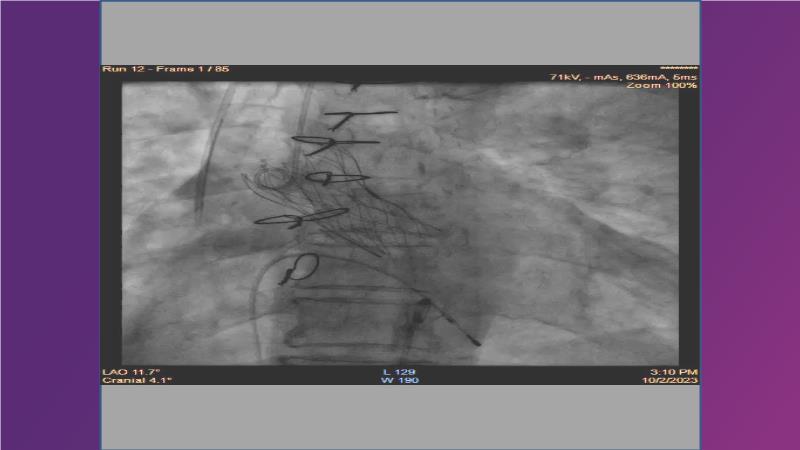

Gain expertise in selecting the appropriate TAVI device for achieving stable deployment in a 90-degree horizontal aorta. Discover techniques for ensuring smooth deliverability, particularly when navigating through tight and tortuous anatomies. Additionally, learn strategies to prepare for future coronary access, irrespective of the height of the left or right coronaries.

• To learn how to select your TAVI device in order to achieve stable deployment in 90 degrees horizontal aorta

• To witness smooth deliverabilty even crossing tight and tortous anatomy